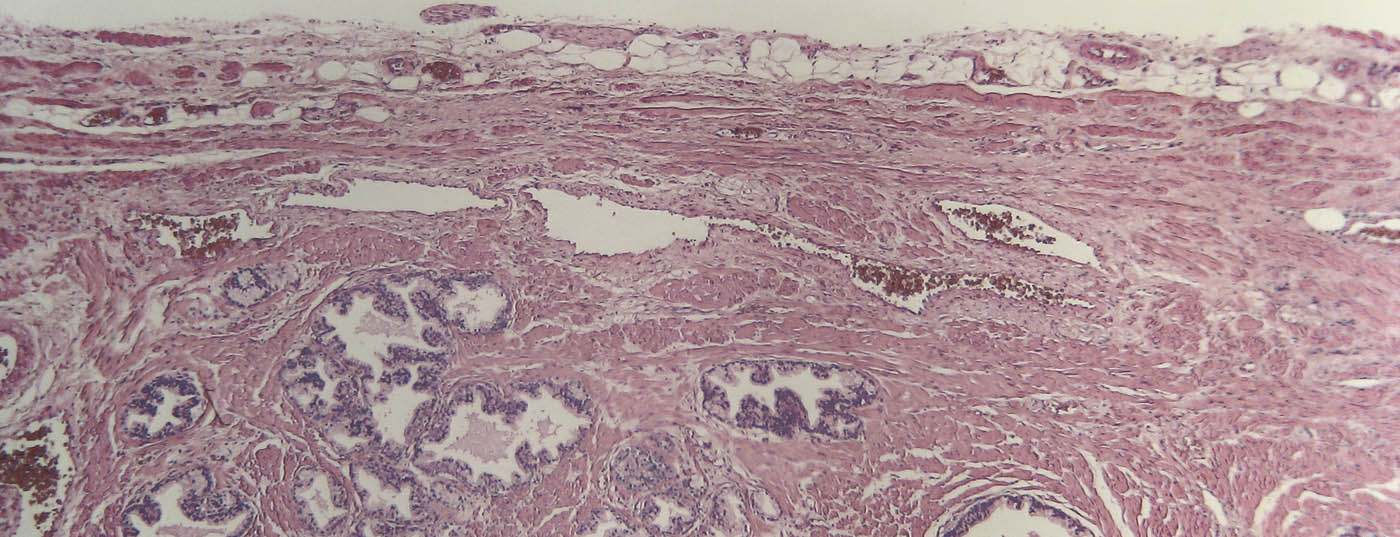

prostata_histo

Risikoabschätzung bei Prostatakrebs: Was leisten Biomarker?

Seit der Implementierung von PSA-Tests hat sich die Anzahl an PCa-Diagnosen vervielfacht. Um Überdiagnose und Übertherapie zu verhindern, werden immer häufiger Biomarker eingesetzt. Über neue Ansätze, aber auch Grenzen mikrobiologischer Tests wurde am Jahreskongress der AUA 2018 diskutiert.